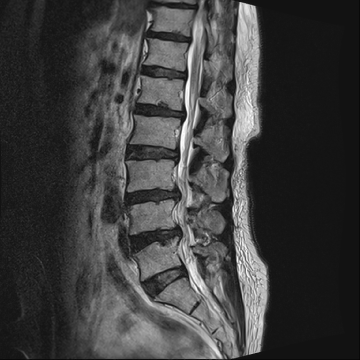

요추 협착증 수술 전·후

2020.08.30

2022.09.06

ㆍ환자 동의를 받은 자료이며, 이미지 사진은 실물과 다를 수 있습니다.

ㆍ모든 자료는 새움병원 자료입니다.